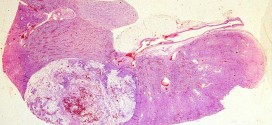

Leer MásADENOCARCINOMA DE CÉLULAS RENALES

El adenocarcinoma de células renales. Tumor maligno en general y especialmente el formado por células epiteliales, se presenta en el parénquima del riñón, es la forma más usual de cáncer y se origina en la proliferación de células epiteliales de los túbulos renales. Hay dos riñones, uno a cada lado de la columna vertebral, por encima de la cintura. Los pequeños …